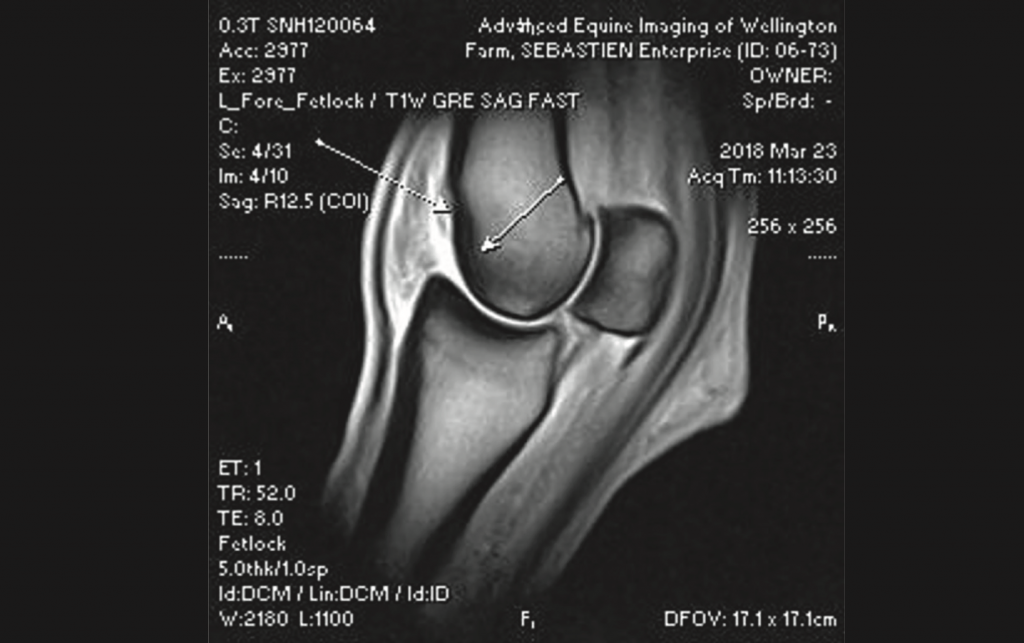

- Mitchell noted that diagnostic blocks regionalized the area and MRI further defined the extent of inflammation and tissue damage.

- Radiographs showed subchondral sclerosis and some changes in the joint margins, indicating some advanced osteoarthritis.